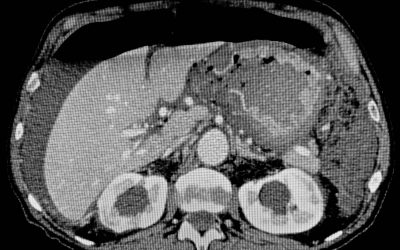

Epatocarcinoma: percorso diagnostico-terapeutico

di Enrico Ganz L’idea di elaborare questo scritto deriva dal desiderio di approfondire alcune questioni relative al trattamento dell’epatocarcinoma, esaminate in un recente convegno, organizzato da alcune Società chirurgiche. Ne ho perciò rivalutato le...